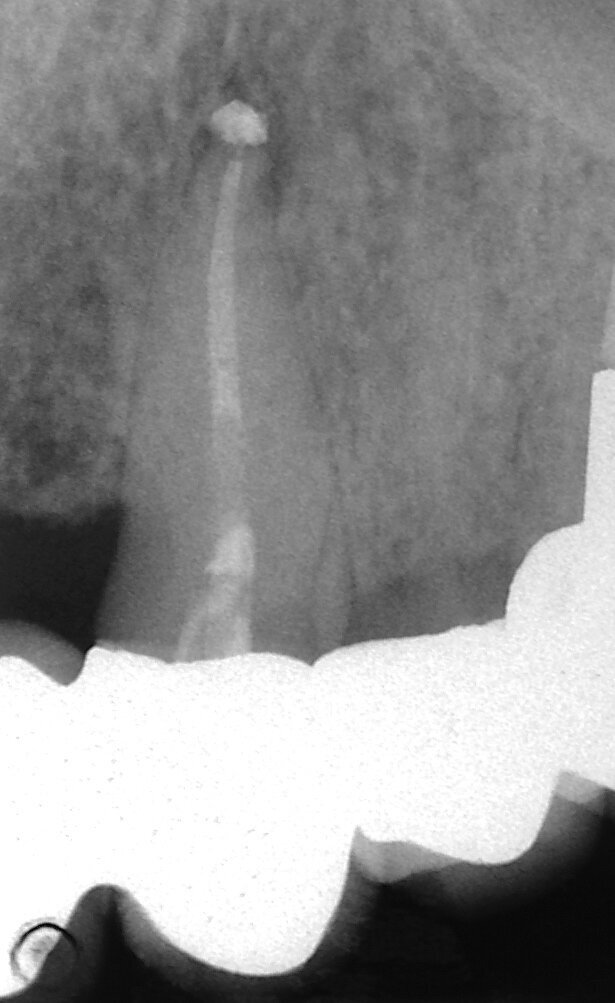

L’incappucciamento della polpa, l’apecificazione, la riparazione delle perforazioni radicolari e l’otturazione dei canali radicolari sono comunemente descritti come procedure cliniche per sigillare il percorso di comunicazione tra il sistema canalare radicolare e la superficie esterna del dente. L’applicazione dell’MTA è stata inizialmente ottenuta con l’ausilio di spatole in plastica o metallo (Torabinejad e Chivian 1999). Sfortunatamente non è stato possibile realizzare in tal modo un posizionamento adeguato (Figg. 1a-1e).

La terapia della polpa vitale è diventata più popolare negli ultimi anni. L’idrossido di calcio è stato il materiale più comune per l’incappucciamento della polpa, ma l’MTA ha mostrato risultati migliori in termini di biocompatibilità e risultati (Aguilar e Linsuwanont 2011). I casi con una grande esposizione della polpa cariosa possono essere trattati con successo con la pulpotomia parziale e l’MTA per l’incappucciamento, mantenendo i denti vitali (Figg. 1a-1e).